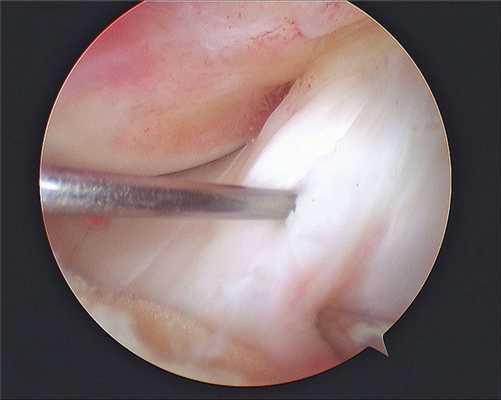

Все артроскопические вмешательства выполняют под визуальным контролем. Для визуализации внутрисуставных структур в суставную полость вводят артроскоп, который представляет собой жестко соединенные между собой трубку и окулярный оголовок. Изображение из артроскопа выводится на экран в операционной, что позволяет хирургу контролировать свои действия, а пациенту — наблюдать за ходом хирургического вмешательства.

Сначала ногу пациента сгибают и через небольшой разрез вводят канюлю. Затем — разгибают и через канюлю вводят артроскоп. Инструменты для артроскопических манипуляций вводят через небольшие разрезы длиной 4-5 мм. После операции артроскоп и все инструменты извлекают, а послеоперационные раны зашивают и заклеивают лейкопластырем.

Операционное поле, можно видеть свечение внутри.

Видео в реальном времени транслируется на экране, выявляет любые существующие дефекты в больном сочленении. Если врач посчитает нужным выполнить регенерацию патологических элементов, он создаст дополнительный разрез (6-8 мм), через который нужным инструментом из микрохирургического набора устранит обнаруженный дефект. Он может сделать частичную резекцию костно-хрящевых тканей, пластику связок и сухожилий, сшивание или удаление (частичное, полное) мениска, экспроприировать хондромные тела, извлечь выпот и гной, ввести противовоспалительные лекарства, взять фрагмент тканей или синовии для изучения их состава и др.